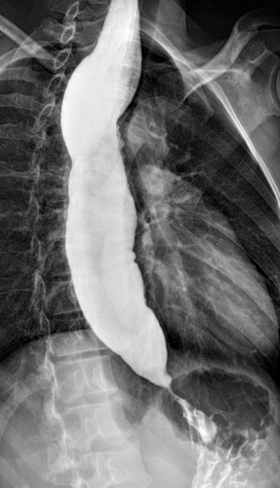

Gastrografin swallow - Colonojejunal anastomosis following esophagogastrectomy for extensive esophageal and gastric burns (Courtesy Dr. V. Penopoulos)